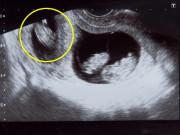

Gần đây dư luận lại được một phen trầm trồ khi mẹ 9X có tên tài khoản mạng xã hội là Hồng Bống chia sẻ về hình ảnh phiếu kết quả siêu âm cho thấy buồng tử cung có 5 túi trống âm. Trong tờ giấy có ghi rõ thông số của từng túi ối với kích thước lần lượt là: 10*11 mm, 11*9 mm, 6*7 mm, 8*6 mm và 10*8 mm.

Phiếu trả kết quả siêu âm của chị Hồng.

Trở về nhà nghỉ ngơi, một tuần sau chị Hồng tiếp tục đến siêu âm ở một đơn vị y tế tư nhân khác, tại đây chị được bác sĩ thông báo có 4 thai, khả năng cao là sẽ có thêm một túi thai nữa, tất cả là 5 túi trống âm với đầy đủ các kích thước khác nhau.

Những miêu tả về túi trống âm được hiện rõ trên phiếu kết quả siêu âm.